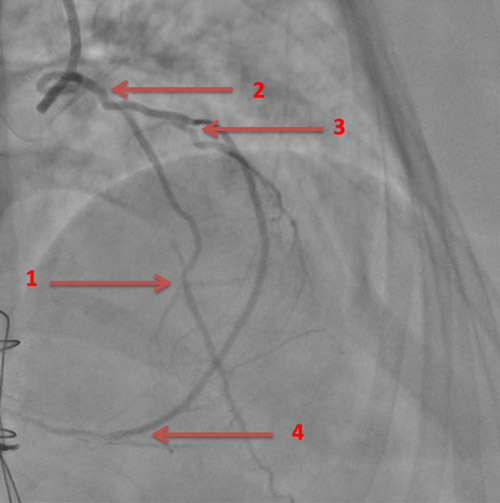

En effet, sur la coronarographie initiale, le réseau natif est quasi occlus, avec une subocclusion longue de l’IVA proximale donnant les premières branches septales, une occlusion chronique de la 2e diagonale, une occlusion chronique de la Cx proximale et de la CD ostiale.

Image 1 : Subocclusion de l’IVA proximale et moyenne (flèches du bas) et occlusion chronique de la 2e diagonale (flèche du haut)

Image 2 : occlusion chronique de la circonflexe proximale

Image 3 : Occlusion chronique de la coronaire droite ostiale

Image 4 :Flèche 1 : anastomose mammaire interne gauche – IVA

Flèche 2 : Mammaire interne droite « branchée en Y » sur mammaire interne gauche

Flèche 3 : anastomose mammaire interne droite – Marginale

Flèche 4 : anastomose mammaire interne droite - IVP